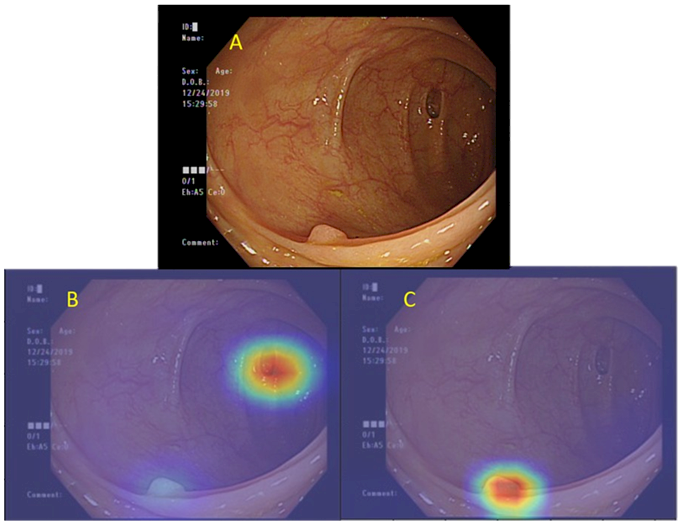

北榮首創ai腸鏡輔助診斷系統多重病灶一次找到 醫療 僑務電子報